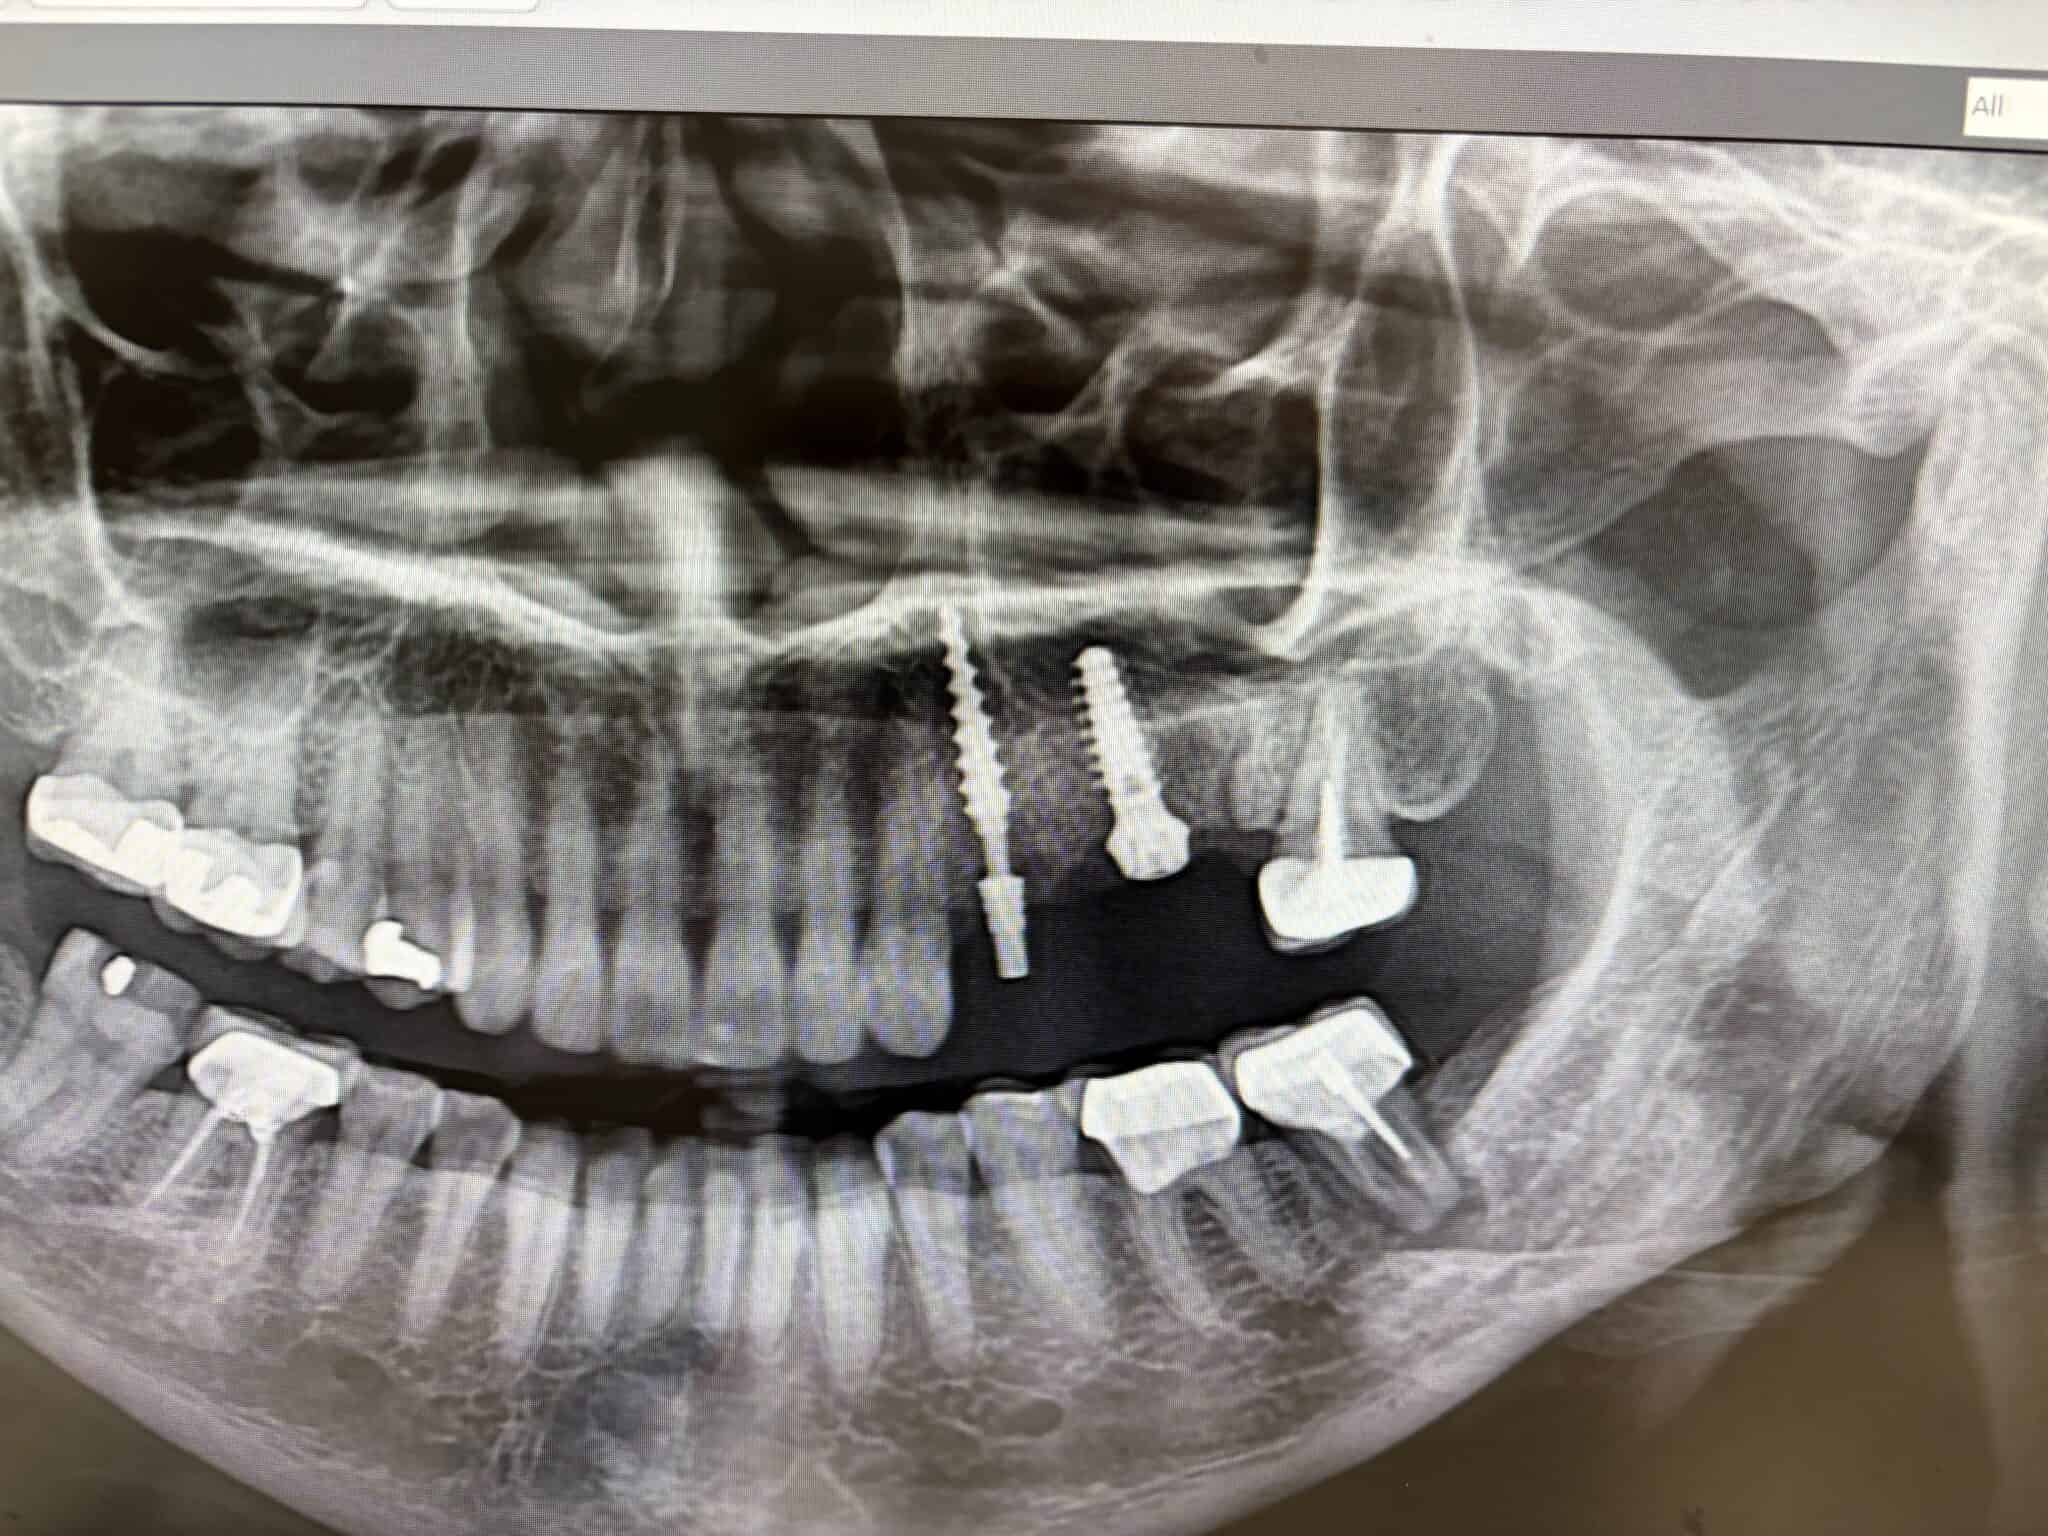

When we refer to a dental implant as โscrewless,โ it is helpful first to visualize the basic structure of a traditional implant. A standard dental implant consists of three main parts that work together. First, there is the implant fixture, a small titanium post that is placed into your jawbone. This fixture acts as an artificial tooth root, bonding naturally with your bone to create a stable foundation for your replacement tooth.

On top of the fixture sits the abutment. This connector rises above your gums and serves as the base for your replacement tooth. In a traditional design, the abutment is attached to the fixture with a tiny screw, which is where the โscrewโ element comes into play. Finally, the visible restoration, a crown, bridge, or denture, attaches to the abutment and functions like a natural tooth.

A screwless implant changes that arrangement. Instead of having a separate abutment connected with a screw, the fixture and abutment are fused together into a single piece. Dr. Chin places the one-piece implant directly into the jawbone with the abutment portion already in place, ready to support the restoration. Since there is no connecting screw between the parts, it earns the name โscrewless.โ